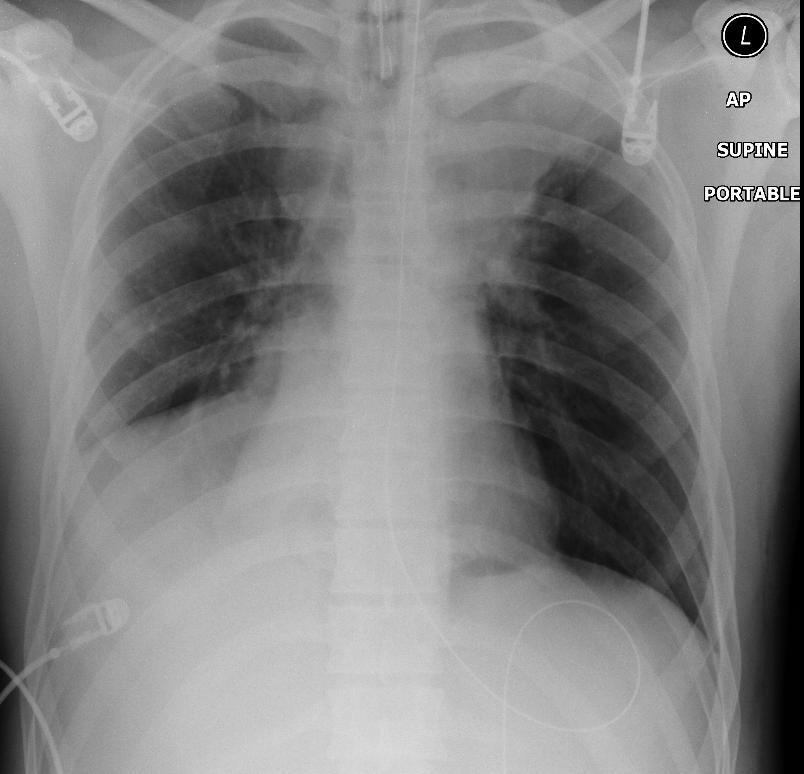

Rib Fractures Supine Haemothorax